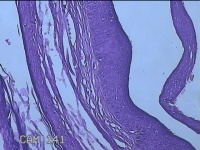

左眼外侧缘上肿物

性别

女

年龄

60岁

临床诊断

痣;疣

左眼上睑缘白色丘疹1年余。

大体所见

图2